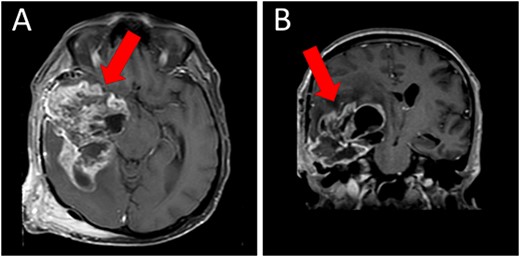

A magnetic resonance imaging (MRI) scan showed extensive hypodense infiltrating disease in the right temporo-parietal region with associated vasogenic edema, alongside a significant space-occupying lesion (Fig. 2).

Preoperative T1WI (A) axial and (B) sagittal MRI images of a huge right temporo-parietal intra-axial lesion (indicated by arrows), which show enhancement after gadolinium injection. The axial image also shows extracranial subgaleal plexiform neurofibroma. MRI = magnetic resonance imaging, T1WI = T1-weighted images